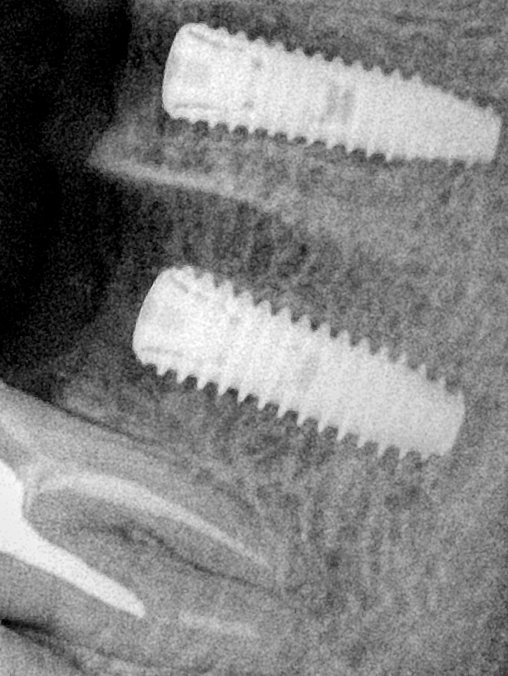

CR/DR 牙齿分割阶段记录

当前进展

- 完成了 CR/DR 牙齿相关分割训练

- 当前结果已经达到阶段预期,但仍有细节问题需要继续处理

相关测试

遇到的问题

- 训练过程中出现过 mask 下移问题

- 部分结果会出现 box 填充异常

- mask 边缘仍然有比较明显的锯齿感

参考

第二版算法问题测试